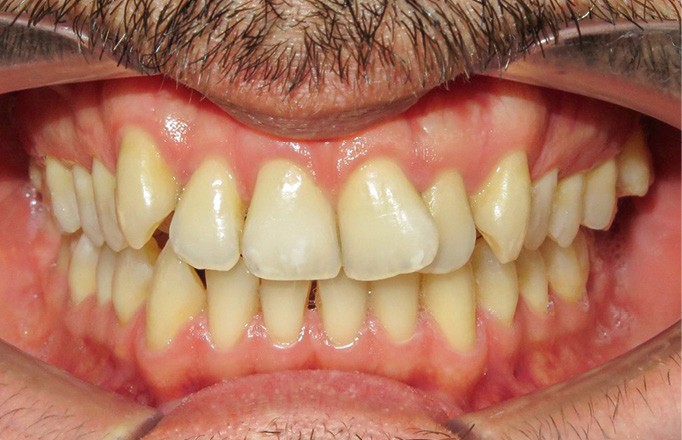

Diagnostic (fig. 1a-i)

Le patient consulte initialement pour des défauts d’alignement. L’examen clinique confirme l’existence d’un encombrement antérieur bimaxillaire, mais révèle aussi la présence d’une Classe II dentaire sévère, d’une exoclusion de la 27 et de troubles parodontaux (peu ou absence de papilles inter-dentaires). Sur le plan squelettique, le patient est relativement équilibré avec un profil harmonieux.